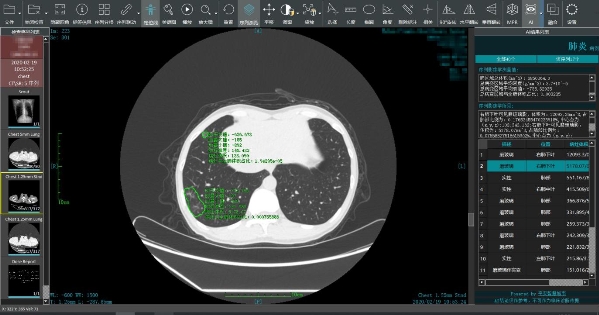

图片说明:平安智慧城市智慧医疗新冠肺炎智能阅片系统为疫区一线进行智能读片,出具智能分析结果

应前线需求,2月19日,平安智慧城市智慧医疗(简称:平安智慧医疗)新冠肺炎智能阅片系统正式上线,该系统支持远程AI读片和电子胶片影像共享,不仅能在15秒左右出具智能分析结果,而且准确率高达90%,可以帮助放射科医生精准识别病灶、在更短的时间内快速出具诊断报告、同时具备电子胶片影像共享功能,减少重复拍片,可以辅助医生尽早发现、快速报告、精准诊断。

平安智慧医疗发挥人工智能科技优势开发的新冠肺炎智能阅片系统,通过人工智能分析引擎,对新冠肺炎CT影像进行智能化分析与定量评价,并对同一患者不同次扫描图像进行对比分析,定量测量病灶的改变情况,辅助医生对患者的病情发展趋势、治疗效果、转归情况等进行智能评估,帮助医生快速、有效的完成对新冠肺炎患者的检出、分诊和评估,辅助医护人员打赢防“疫”战。